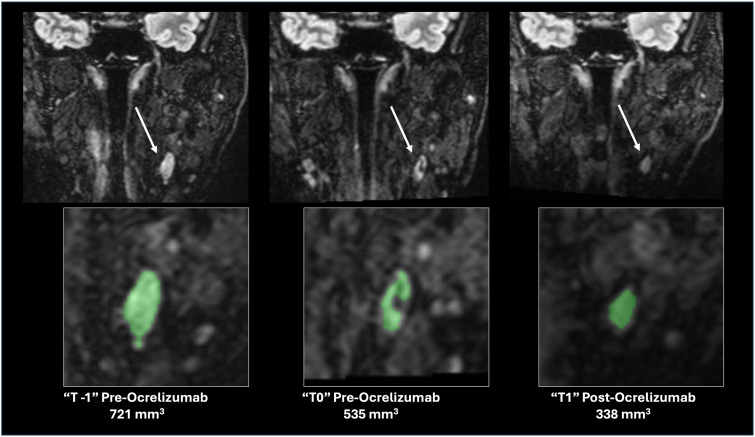

颈深淋巴结(dcln)是免疫呈递和脑b细胞成熟的部位,可能参与神经炎症机制。我们假设在b细胞耗竭治疗后dCLN体积减少。在一项回顾性队列研究中,我们在“基线前”、“基线”和“b细胞耗竭后”时间点通过T2-FLAIR MRI对双侧dCLN进行了分割。使用多变量混合效应回归模型,我们发现基线前和基线时间点之间dCLN体积没有变化(p < 0.05),但ocrelizumab输注后dCLN体积显著减少158 mm3 (t = -3.3, p = 0.005)。基线使用疾病修饰治疗也与较小的dCLN体积和减轻b细胞耗竭的影响显着相关。这些结果与治疗机制一致,尽管基于这些数据不能排除dCLN体积减少的其他替代解释。深CLN代表了潜在的药理或临床应用的成像生物标志物,值得进一步研究。

The deep cervical lymph nodes (dCLNs) are sites of immune presentation and B-cell maturation from the brain, and potentially involved in mechanisms of neuroinflammation. We hypothesized a reduction in dCLN volume following B-cell depletion therapy. In a retrospective cohort, we segmented bilateral dCLN from T2-FLAIR MRI at "prebaseline," "baseline," and "post-B-cell depletion" timepoints. Using a multivariable mixed-effect regression model, we find no changes in dCLN volumes between prebaseline and baseline timepoints (p > 0.05), but a significant decrease of 158 mm3 following ocrelizumab infusion (t = -3.3, p = 0.005). Baseline use of a disease-modifying therapy was also significantly associated with a smaller dCLN volume and attenuated the effects of B-cell depletion. These results are congruent with therapeutic mechanisms, although other alternative explanations for reductions in dCLN volumes cannot be ruled out based on this data. Deep CLN represent potential imaging biomarkers of pharmacological or clinical utility and warrant further investigation.